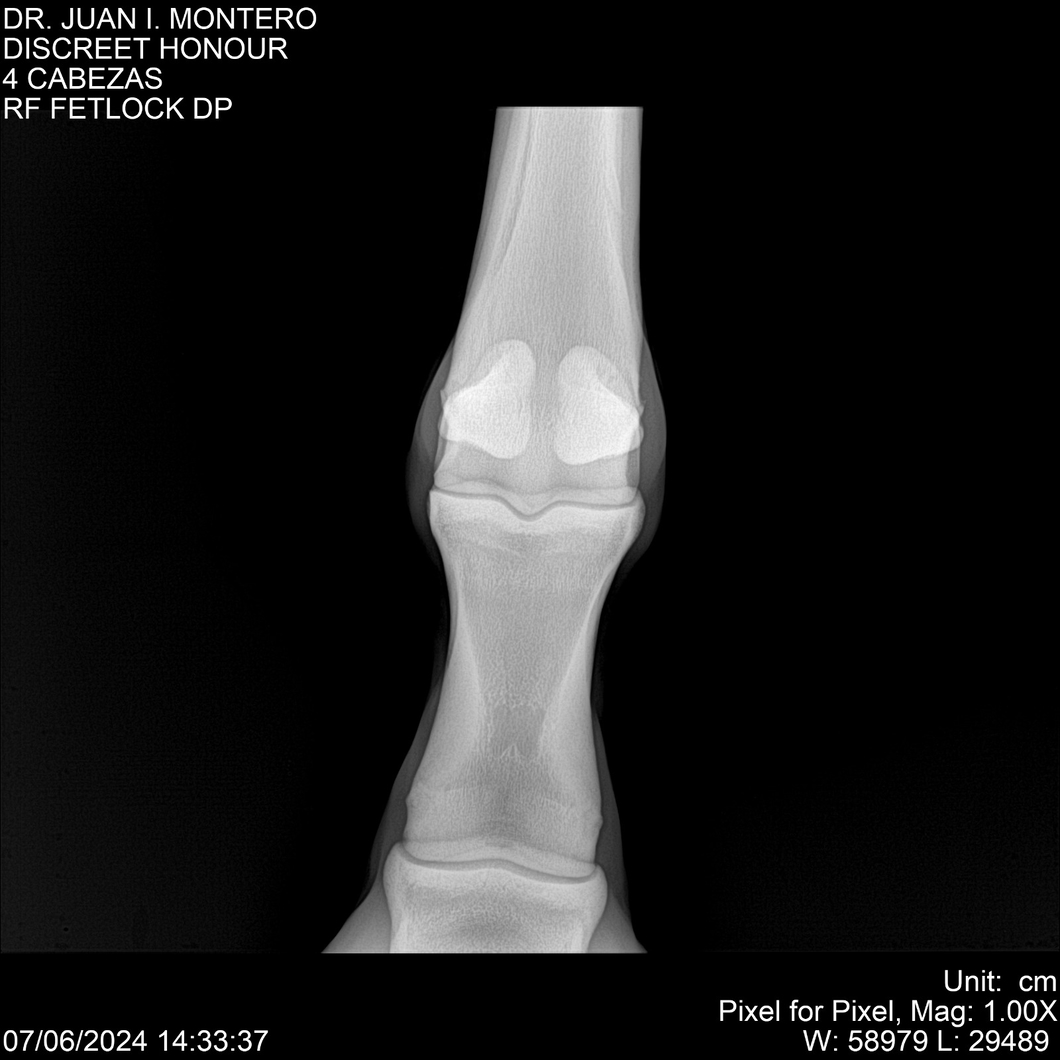

LOTE 6, DISCREET HONOUR 🔥 🔥 🔥 Lote Anterior Volver al remate Lote Siguiente Ficha Contacto Montevideo - Ficha del Lote Identificador: #281093 Categoría: Yeguarizos Montevideo - 82 Visualizaciones ClicData Contacto Empresa: Abelenda N. R., Walter Hugo Nombre*: Teléfono* : E-mail* : Mensaje Enviar Registrese gratis Este contenido Exclusivo está disponible sólo para usuarios registrados Ingresar